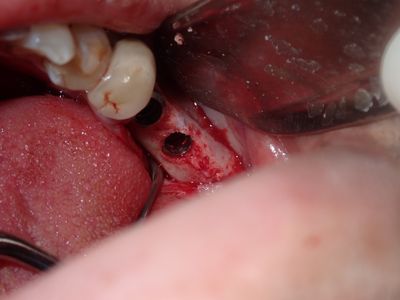

relatively straight forward implant placement, some bone expansion and countersinking. buccal bone thin, grafted with sticky bone from allograft folloewd by collagen mmebrane soaked in prf fluid, additional fibrin membrane used